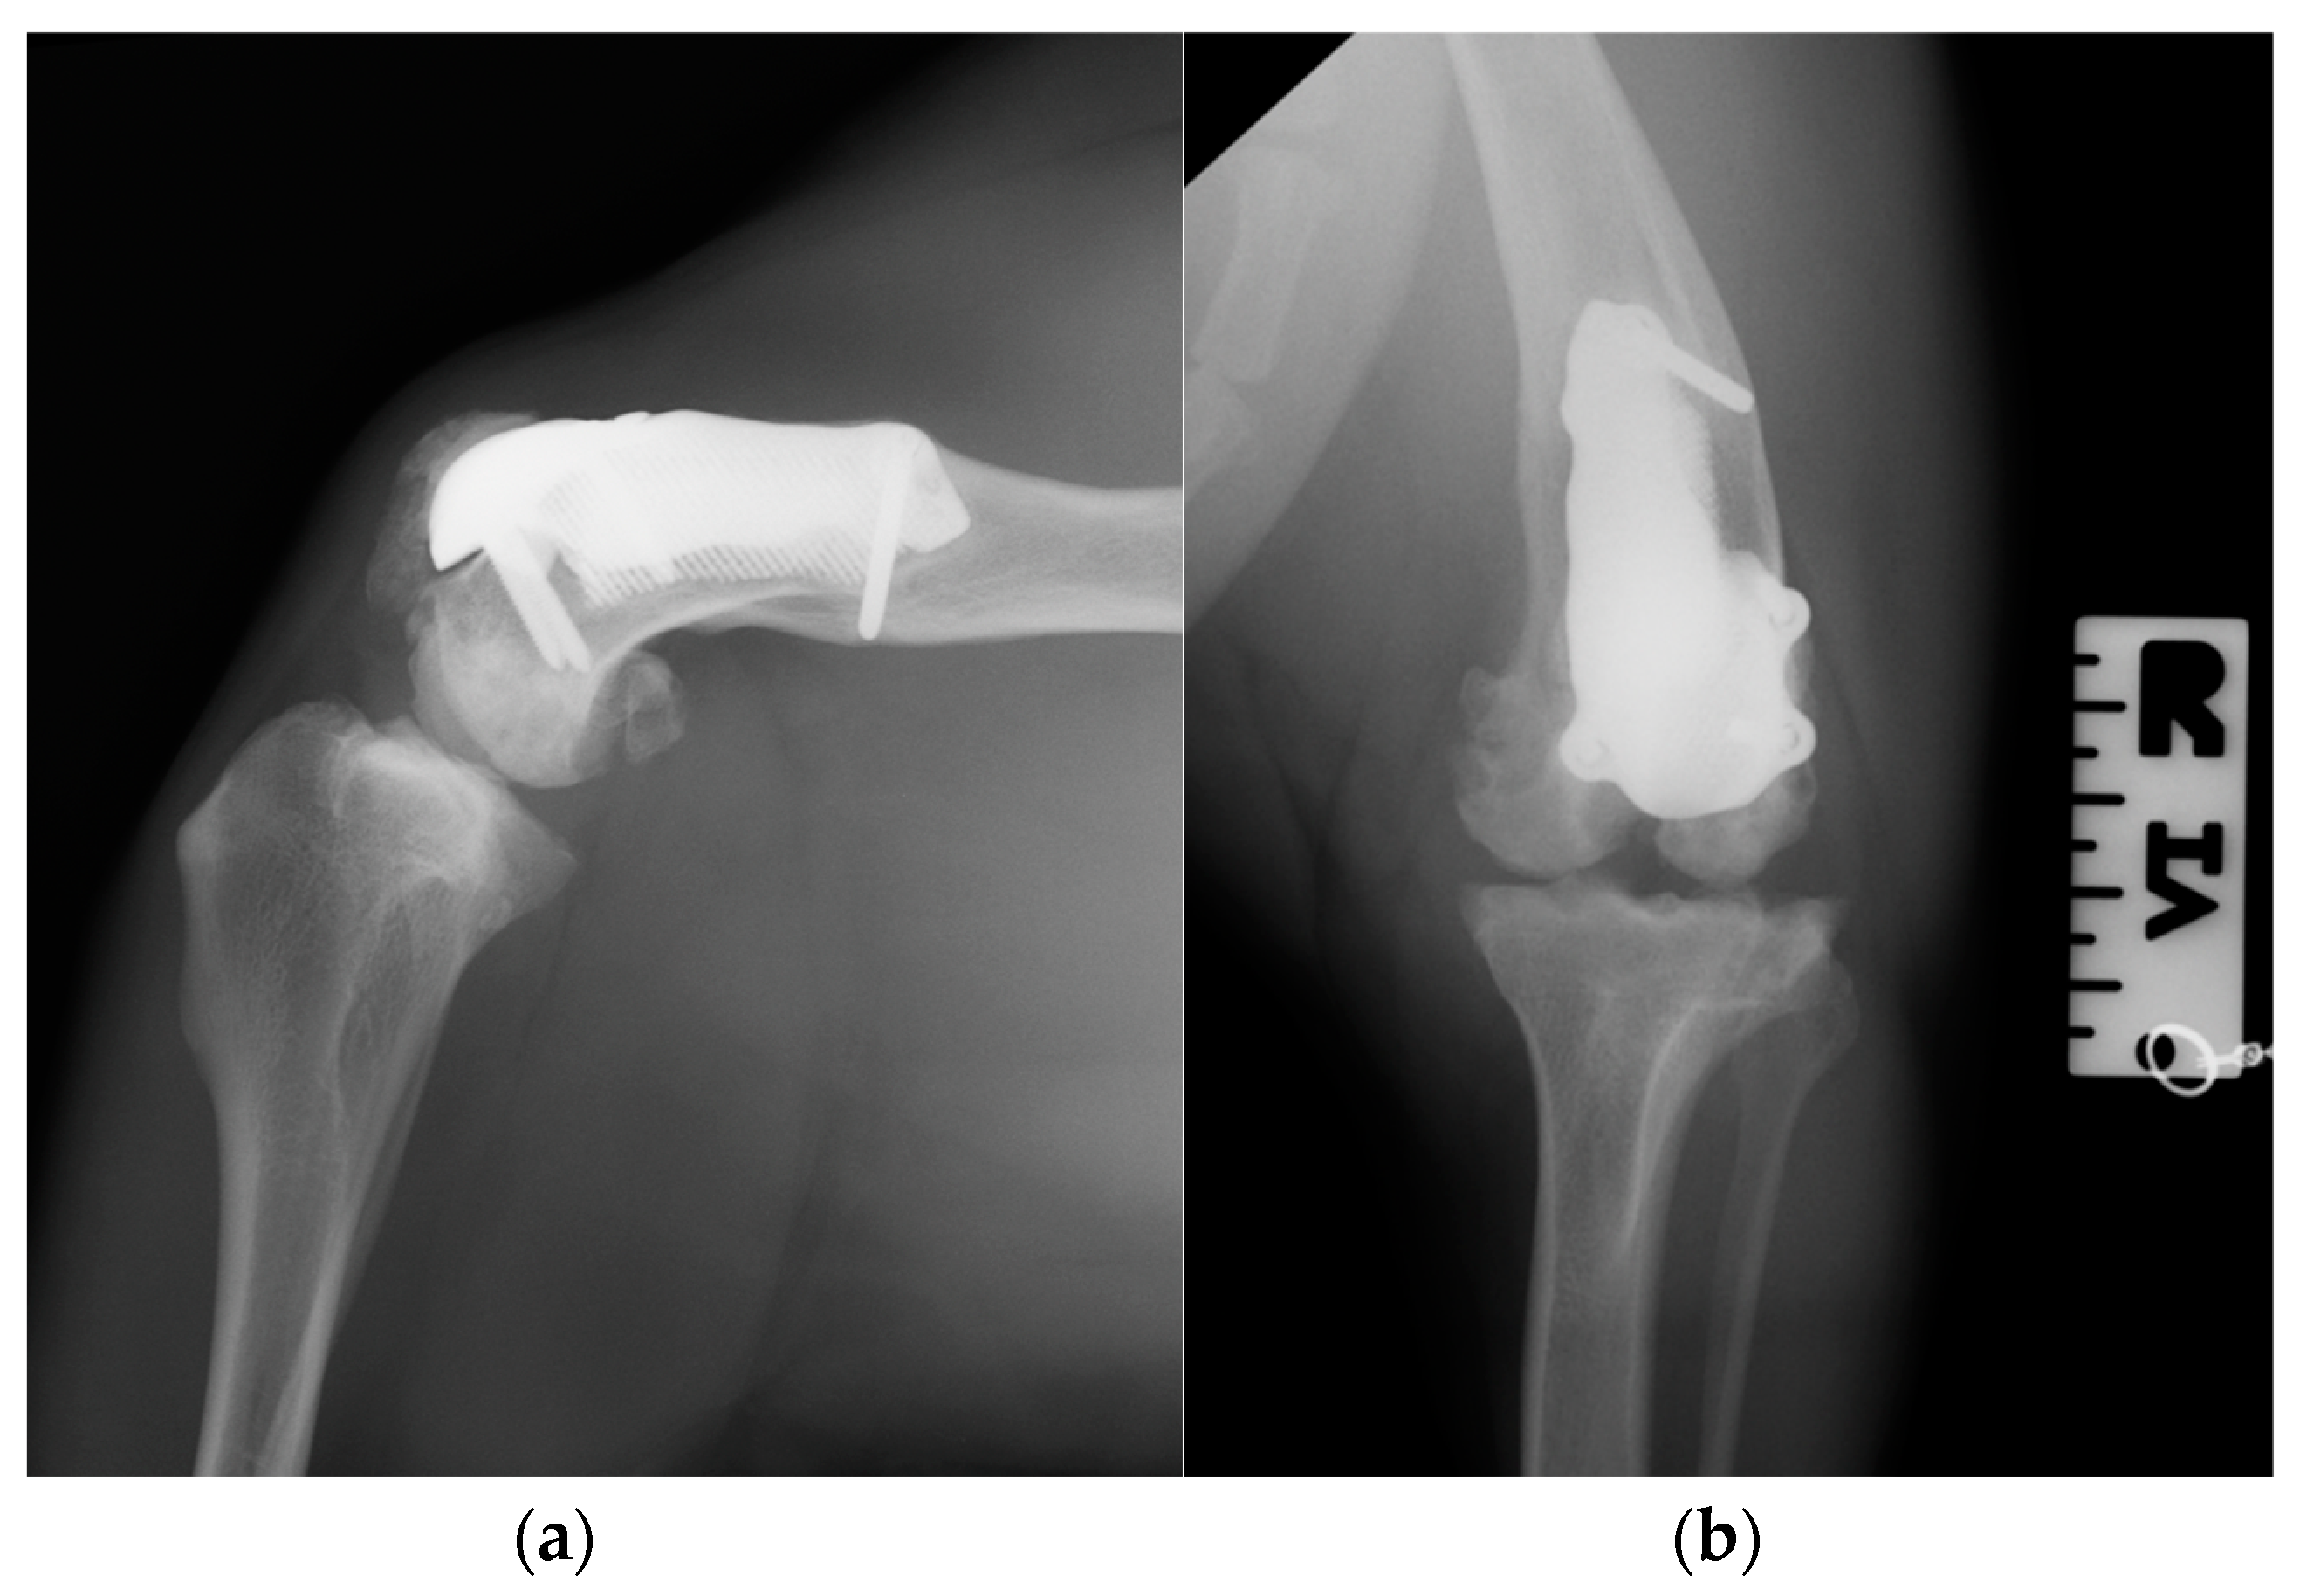

Postoperative medio-lateral and caudo-cranial radiographs of the stifle joint were performed to evaluate the proper prosthesis position, the length of the screws and to confirm the patellar reduction (Figure 10). To improve the postoperative assessment, CT scans of the right stifle joint were obtained. A modified Robert-Jones splint was applied for 24 hours postoperatively. Meloxicam (0,1 mg/kg) once a day and amoxicillin and clavulanic acid (20 mg/kg) twice a day were prescribed for 10 days and only short walks on the leash to be gradually increased during the two months post-operative rehabilitation was recommended.

Figure 10. Postoperative medio-lateral (a) and caudo-cranial (b) radiographs of the stifle joint showed the appropriate prosthesis position, the correct length of the screws and the reduction of the patella.